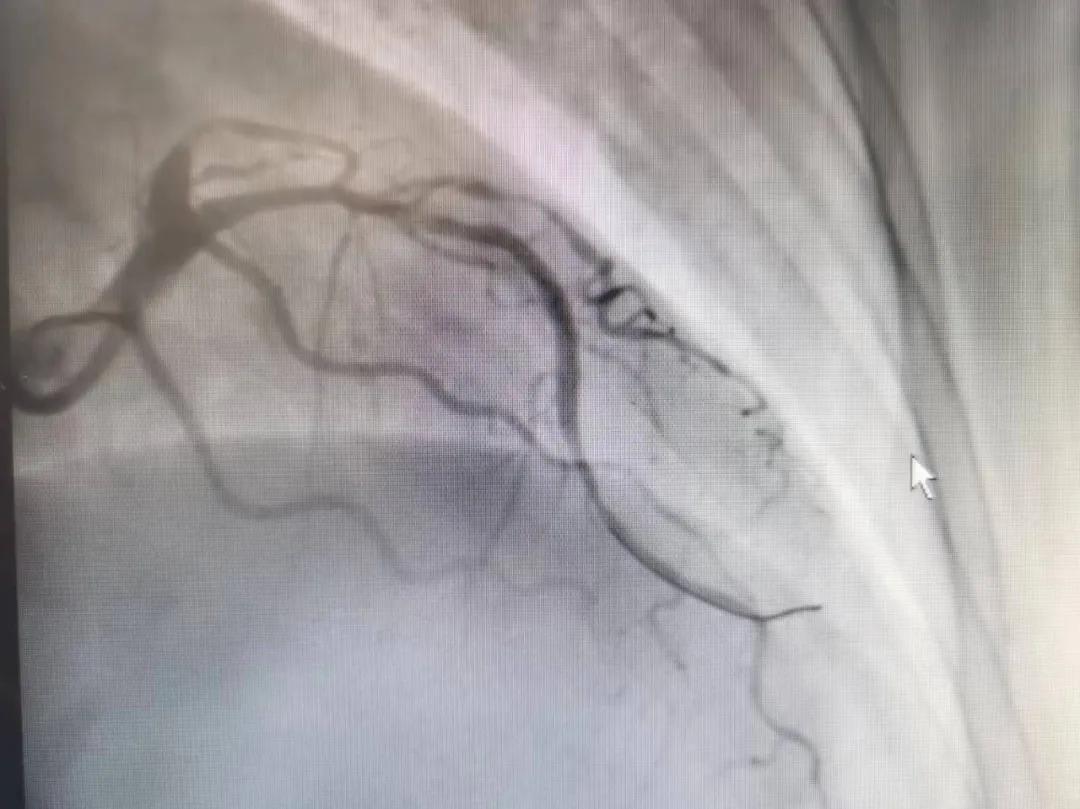

術(shù)前

王瑾院長(zhǎng)和李慧新主任帶領(lǐng)介入團(tuán)隊(duì)充分評(píng)估,決定行前降支冠狀動(dòng)脈鈣化病變旋磨術(shù),術(shù)中應(yīng)用1.5mm旋磨頭,以15萬(wàn)-17萬(wàn)轉(zhuǎn)/分速度共對(duì)病變旋磨3次,累計(jì)旋磨時(shí)間60秒,后復(fù)查造影示鈣化明顯減輕,為后續(xù)操作創(chuàng)造了良好條件,隨后應(yīng)用預(yù)擴(kuò)張球囊、切割球囊再次處理病變,并順利植入支架1枚,復(fù)查造影顯示支架膨脹及貼壁良好,無(wú)夾層、血腫、慢血流等情況,手術(shù)順利完成?;颊咝g(shù)后無(wú)不適,胸悶、胸痛癥狀明顯緩解,順利出院。